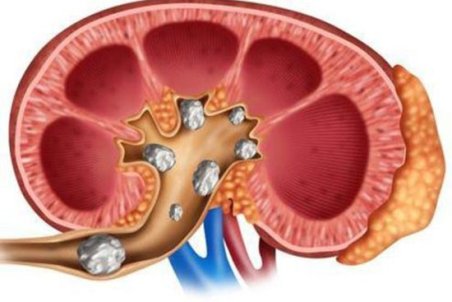

سنگ کلیه جسم سختی است که از موادشیمیایی در ادرار تشکیل شده. انواع متعددی دارد،اما همه دارای علائم مشابهی هستند که می تواند بسیار دردناک باشند،به ویژه اگر سنگ کلیه به مرور زمان رشد کرده باشد.

یکی از مشکلات کلیوی رایج سنگ کلیه می باشد که از مواد معدنی و نمکی در دستگاه ادراری تشکیل می شود. یکی از راه هایی که مورد توجه افراد بسیاری قرار می گیرد استفاده از داروهای گیاهی برای سنگ کلیه می باشد که در این مقاله به معرفی آنها می پردازیم.

تجمع بیش از حد املاح در کلیهها میتواند منجر به تشکیل سنگهایی به شکل کریستال شود که اگر دفع نشوند، میتوانند عوارضی چون عفونت یا آسیبهای کلیوی را بهدنبال داشته باشند.

معمولاً سنگهای کلیه کوچک، بدون بروز علائم و مشکلات خاصی دفع میشوند اما سنگهای بزرگتر در مجاری ادراری لانه میکنند و منجر به درد میشوند؛ اگر این سنگها دفع نشوند، میتوانند عوارضی چون عفونت یا آسیبهای کلیوی را بهدنبال داشته باشند.